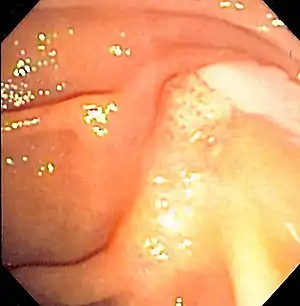

| Duodenoscopy image of pus extruding from the ampulla of Vater, indicative of cholangitis | |

The gold standard test for biliary obstruction is still endoscopic retrograde cholangiopancreatography (ERCP). This involves the use of endoscopy (passing a tube through the mouth into the esophagus, stomach and thence to the duodenum) to pass a small cannula into the bile duct. At that point, radiocontrast is injected to opacify the duct, and X-rays are taken to get a visual impression of the biliary system. On the endoscopic image of the ampulla, one can sometimes see a protuberant ampulla from an impacted gallstone in the common bile duct or the frank extrusion of pus from the common bile duct orifice. On the X-ray images (known as cholangiograms), gallstones are visible as non-opacified areas in the contour of the duct. For diagnostic purposes, ERCP has now generally been replaced by MRCP. ERCP is only used first-line in critically ill patients in whom delay for diagnostic tests is not acceptable; however, if the index of suspicion for cholangitis is high, an ERCP is typically done to achieve drainage of the obstructed common bile duct.[1]